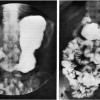

Duodenal cap Definition It is the first section of the duodenum, or the part of the small intestine within the jejunum and the stomach. It can be seen by fluoroscopy or with the aid of a roentgenogram. This intestinal structure is also referred to as “Pyloric cap.” Duodenal cap Appearance This structure is about 2 cms […]